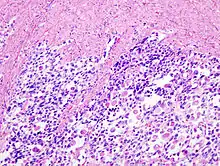

Invasion du myomètre par un carcinosarcome utérin avec différenciation rhabdomyosarcomateuse. HE, x400